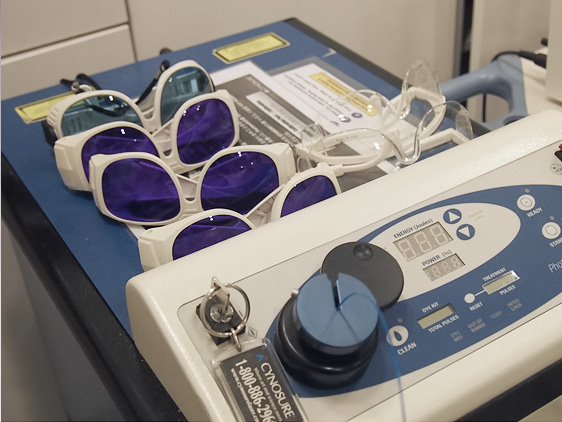

퍼져있는 등의 경우에는 PDL레이저를 병행해서 사용하기도 합니다.